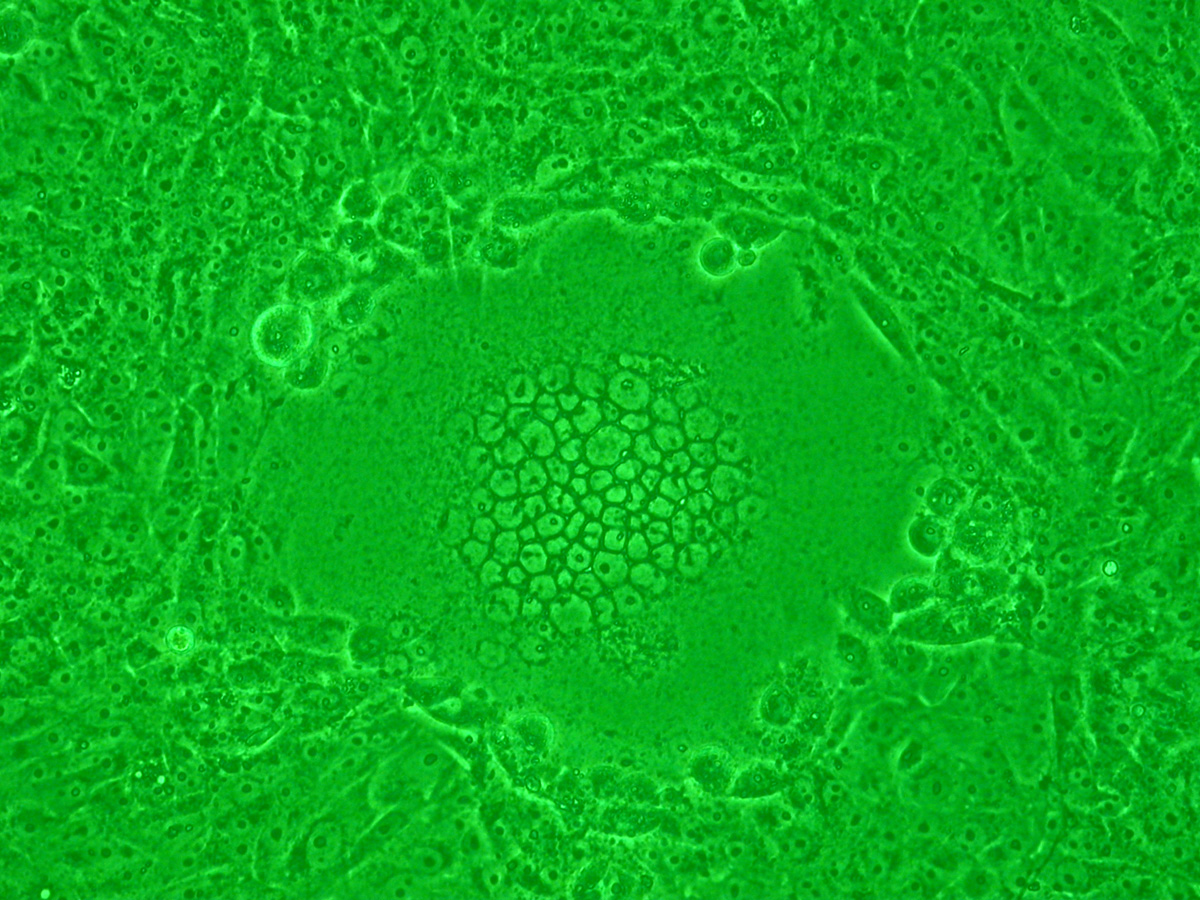

융단 모양으로 성장한 배양 세포가 바이러스에 감염되면 세포막 융합이 일어나 세포핵이 중앙에 응집, 다핵 거대 세포(사진 중앙)가 된다.]]

합포체는 여러 바이러스 감염 시 세포 융합으로 형성될 수 있다. 특히 사람 헤르페스 바이러스, 인간 면역 결핍 바이러스(HIV), 파라믹소바이러스(RSV 등)가 이러한 합포체 형성을 유발한다. 세포 융합은 바이러스 침입 후 감염 세포의 세포막 표면에 발현된 바이러스 막 단백질 작용으로 발생한다(fusion from within). 또는 바이러스 입자가 숙주 세포의 세포막에 결합하여 침입할 때 인접 세포끼리 융합(fusion from without)되면서 발생하기도 한다.

융단 모양으로 성장한 배양 세포끼리 바이러스 감염에 의해 세포막의 융합이 일어나 세포핵이 중앙에 응집하여 (사진 중앙) 다핵 거대 세포 형태가 된다.

합포체는 다양한 바이러스 감염 시 세포 융합으로 형성될 수 있다. 특히 사람 헤르페스 바이러스나 인간 면역 결핍 바이러스(HIV), 파라믹소바이러스(예: RS 바이러스(RSV))가 이러한 합포체 형성을 유발한다. 세포 융합은 바이러스가 침입한 후 감염 세포의 세포막 표면에 발현된 바이러스 막 단백질의 작용으로 발생하거나(fusion from within), 바이러스 입자가 숙주 세포의 세포막에 결합하여 침입하려고 할 때 인접 세포끼리 융합(fusion from without)되면서 발생한다. 인간 면역 결핍 바이러스 등의 레트로바이러스나, 헤르페스 바이러스에서는 전자의 경우만, 센다이 바이러스로 대표되는 파라믹소바이러스에서는 두 가지 현상 모두 관찰된다. 합포체 형성은 바이러스 감염을 나타내는 세포 형태 변화(세포변성효과) 중 하나로, 바이러스학 분야에서 활용된다.